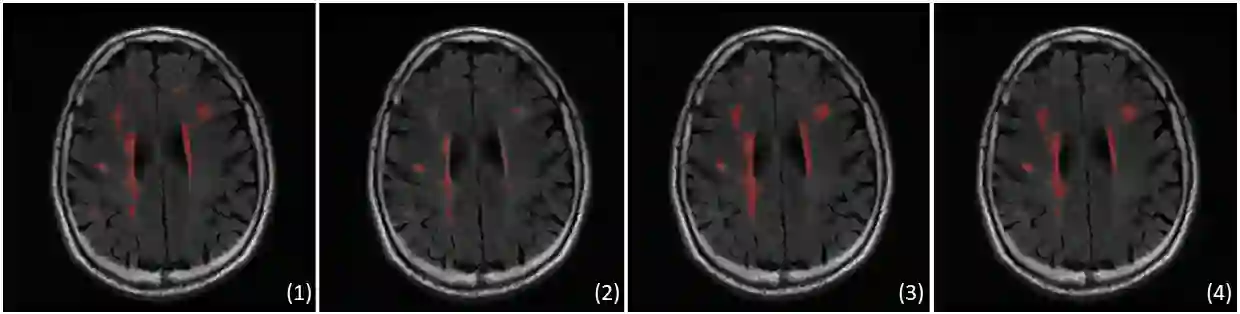

We propose an unsupervised domain adaptation (UDA) approach for white matter hyperintensity (WMH) segmentation, which uses Self-Training with Uncertainty DEpendent Label refinement (STRUDEL). Self-training has recently been introduced as a highly effective method for UDA, which is based on self-generated pseudo labels. However, pseudo labels can be very noisy and therefore deteriorate model performance. We propose to predict the uncertainty of pseudo labels and integrate it in the training process with an uncertainty-guided loss function to highlight labels with high certainty. STRUDEL is further improved by incorporating the segmentation output of an existing method in the pseudo label generation that showed high robustness for WMH segmentation. In our experiments, we evaluate STRUDEL with a standard U-Net and a modified network with a higher receptive field. Our results on WMH segmentation across datasets demonstrate the significant improvement of STRUDEL with respect to standard self-training.